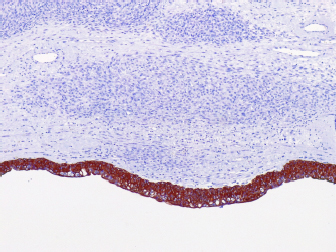

Table 2. Canine blood gas parameters in the perioperative and postsurgical analysis*.

Similar to the findings in human medicine (Chen et al., 2008), malignant neoplasms in the urinary tract are commonly located in the distal portion of the ureter (Berzon, 1979; Hanika & Rebar, 1980; Polit et al., 2020), whereas benign neoplasms affect the proximal region (Hattel et al., 1986; Burton et al., 1994). In the present report, the ureteral leiomyosarcoma was located in the proximal ureter. The exact location of the neoplasm was obtained only through exploratory laparotomy because the abdominal ultrasound was inconclusive, and the owner declined computed tomography. Furthermore, normal urothelial mucosa in the ureter was observed by IHC for pan-cytokeratin (Fig. 5), whereas below the urothelial mucosa, mesenchymal cell proliferation was negative. In the histopathological examination, it was also possible to determine that in the kidney sample, we did not have neoplastic cells, whereas in neoplastic tumors, the intact ureter epithelium was present, indicating a urinary origin and possibly an origin from the ureteral wall, as we did not observe any other structures that would suggest neoplastic tissue originating from the kidney.

Fig. 3. Photomicrographs of a canine ureteral leiomyosarcoma. (A) Positive staining for GATA3 in normal urothelial mucosa in the ureter, 20x. (B) Staining for UPIII in normal urothelial mucosa in the ureter, 20x. (C) Positive staining for alpha-smooth muscle actin (1A4) in neoplastic cells, 10x. (D) Positive staining for muscle-specific actin, 10x. (E) Positive staining for smooth muscle myosin heavy chain, 40x. (F) Scatted positive staining for desmin, 10x. IHC, Harris hematoxylin counterstaining.

Fig. 5. Photomicrographs of a canine ureteral leiomyosarcoma. (A) Positive staining for pancytokeratin (AE1AE3) in normal urothelial mucosa in the ureter with negative staining of mesenchymal cell proliferation below, 10x.